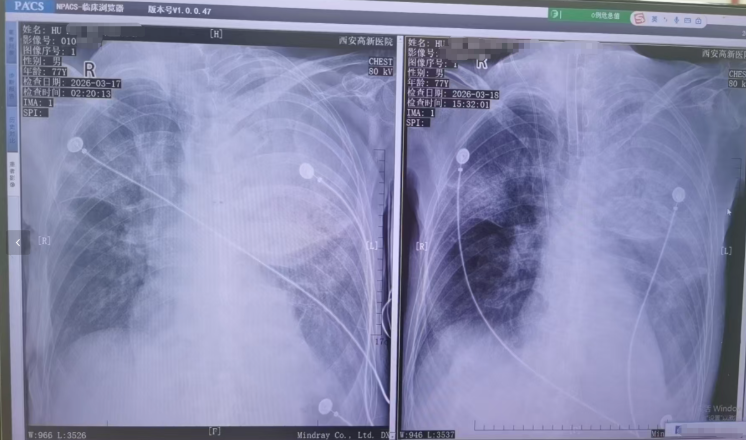

▲患者接受转院治疗

胡先生说,起初以为是感冒,住院治疗没有效果,还越来越严重,以至于病情危重,“整个肺部全白了”,并且出现呼吸衰竭,医院甚至下了病危通知书。3月17日,家人赶紧将父亲转院到西安高新医院抢救,到医院以后就住进了ICU。经检查,才发现是鹦鹉热衣原体感染导致的重症肺炎。胡先生提供的一份《西安高新医院诊断证明》显示,胡先生的父亲3月17日以重度肺炎入院。诊断为重症肺炎(鹦鹉热衣原体感染)I型呼吸衰竭,急性呼吸窘迫综合征,脓毒症等。

▲患者胸片